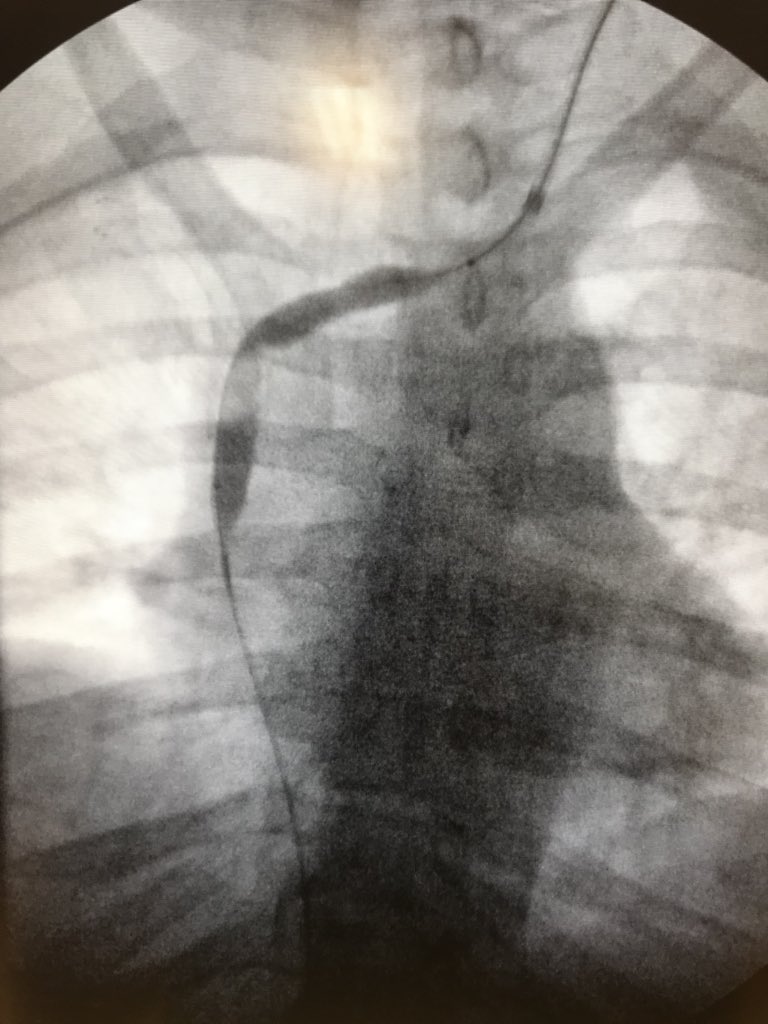

New study @AnnalsofIM bit.ly/2Km3KYu by @DrTalenfeld @WeillCornell: Percutaneous ablation for T1a #renalcancer has similar 5-year survival rates to radical nephrectomy but with far fewer 30-day complications and less #kidneyfailure.